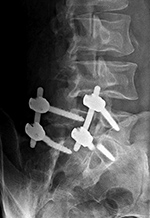

Lumbar spine bony disk strut, pedicle screws, and pedicle rods (lateral view) |

There are also bilateral pedicle screws and connecting rods above and below the level of the fracture. |

20 year-old woman with L1 vertebral body compression fracture treated with T12-L2 posterior spinal fusion using pedicle screws at T12 and L2 with connecting rods on each side. |